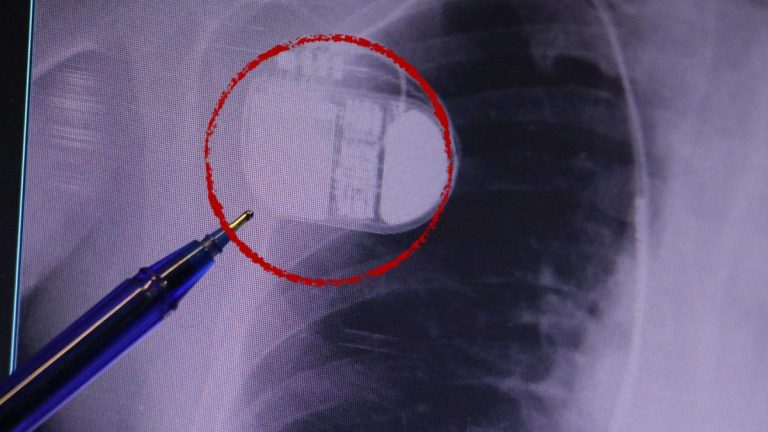

Gençlerde ani ölümler artıyor! Uzman nedenini açıkladı